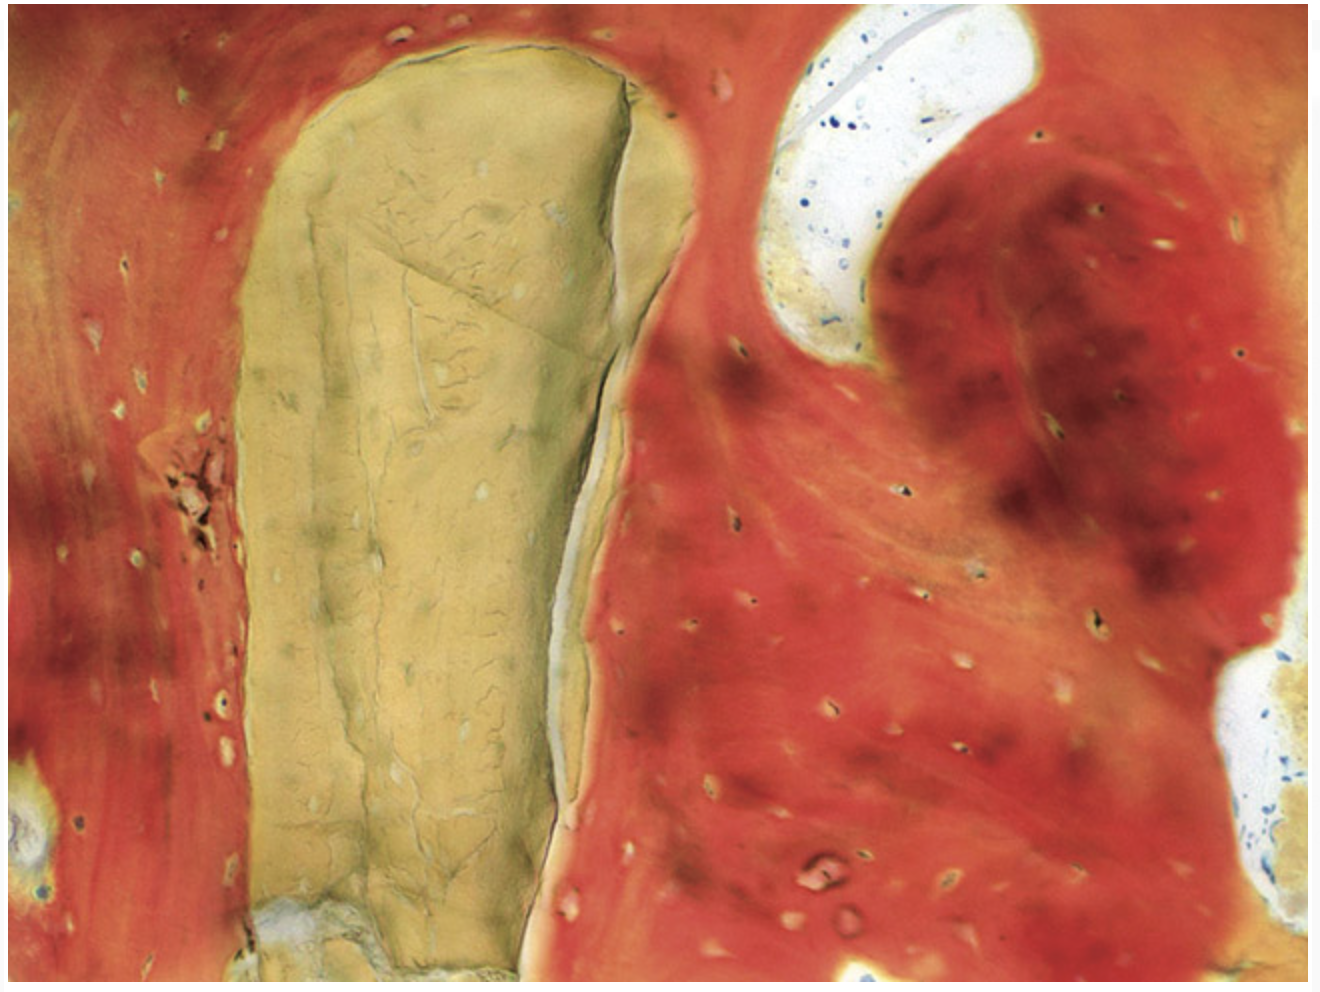

Figure 23  Trephinated core biopsy obtained at 5 months.

Figure 23

Figure 24  Histology: Note active osteocytes with new bone formation.

Figure 24

A 72-year-old man was referred for removal of failing maxillary right posterior implants (Figure 19). The treatment plan included removal of three implants with simultaneous bone augmentation and replacement implants for implant-supported fixed bridgework. Implant removal and bone grafting with rhPDGF (Gem 21®, Osteohealth, www.osteohealth.com) and allograft (MinerOss) and xenograft (BioOss®, Geistlick, www.geistlickonline.com) were used along with titanium mesh for space maintenance (Figure 20, Figure 21 and Figure 22). Six months later, mesh removal revealed type I bone allowing for placement of three implants (Figure 23 and Figure 24).